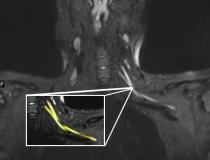

This photo gallery shows the variety of radiological presentations of COVID-19 (SARS-CoV-2) in medical imaging, including computed tomography (CT), radiograph X-rays, ultrasound, echocardiograms and magnetic resonance imaging (MRI). The radiology images show examples of typical COVID pneumonia in the lungs and the numerous complications the virus causes in the body in multiple organs, including the brain, kidneys, heart, abdomen and vascular system.